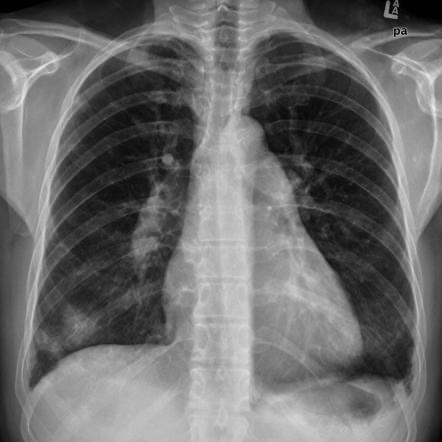

폐고혈압의 Chest Xray 소견

• Prominent pulmonary artery + central pulmonary vasculature (점선)

• Elevated LV apex (due to RVH), water bottle shape

• RA enlargement (화살표)

• peripheral vascular marking 감소 (vascular pruning)

+ Left heart disease에 의한 폐울혈이 있을 경우 LAE/LVH, pulmonary edema, pleural effusion 동반

+ Lung disease가 있을 경우 diaphragm flattening, hyper lucency, reticular opacity 동반